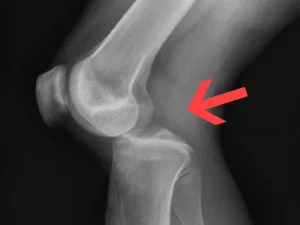

پارگی منیسک زانو یکی از شایعترین آسیبهای زانو است که